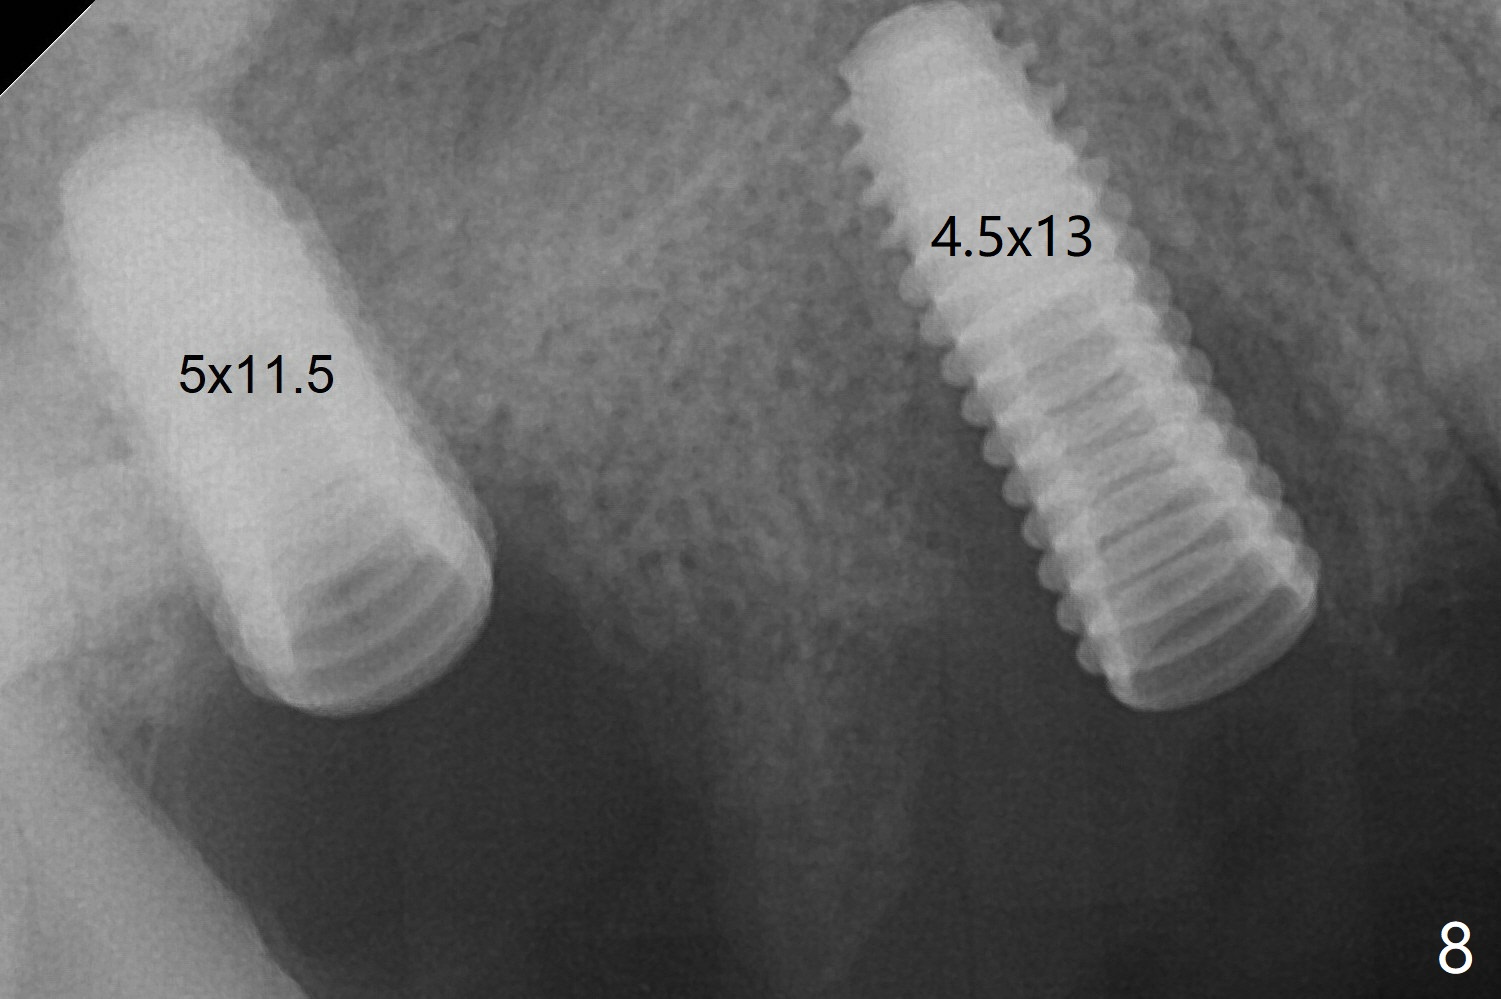

Then a 5x11.5 mm is placed at #3 subcrestal proximally after sinus lift with Vanilla graft (without sinus membrane perforation; Fig.8). The implants seem to have been osteointegrated 4.5 months postop (Fig.11). The 6.5x7(5) and 5.5x4(5) mm abutments are parallel.